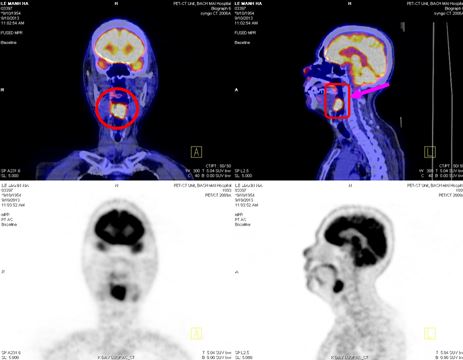

Trên hình ảnh PET/CT:

- Vùng đáy lưỡi có khối lớn kéo dài đến thanh quản kích thước: 2,4x3,6x2,9cm, tăng hấp thu F18- FDG max SUV=8,28.

- Hạch góc hàm trái kích thước: 1,9cm, tăng hấp thu F18- FDG max SUV=6,89. Hạch góc hàm phải kích thước: 1,8cm, max SUV=5,28. Hạch cảnh giữa phải kích thước: 1,3cm, max SUV=4,42.

Hình 3. Hình ảnh khối u vùng đáy lưỡi di căn hạch cổ hai bên trên hình ảnh PET/CT